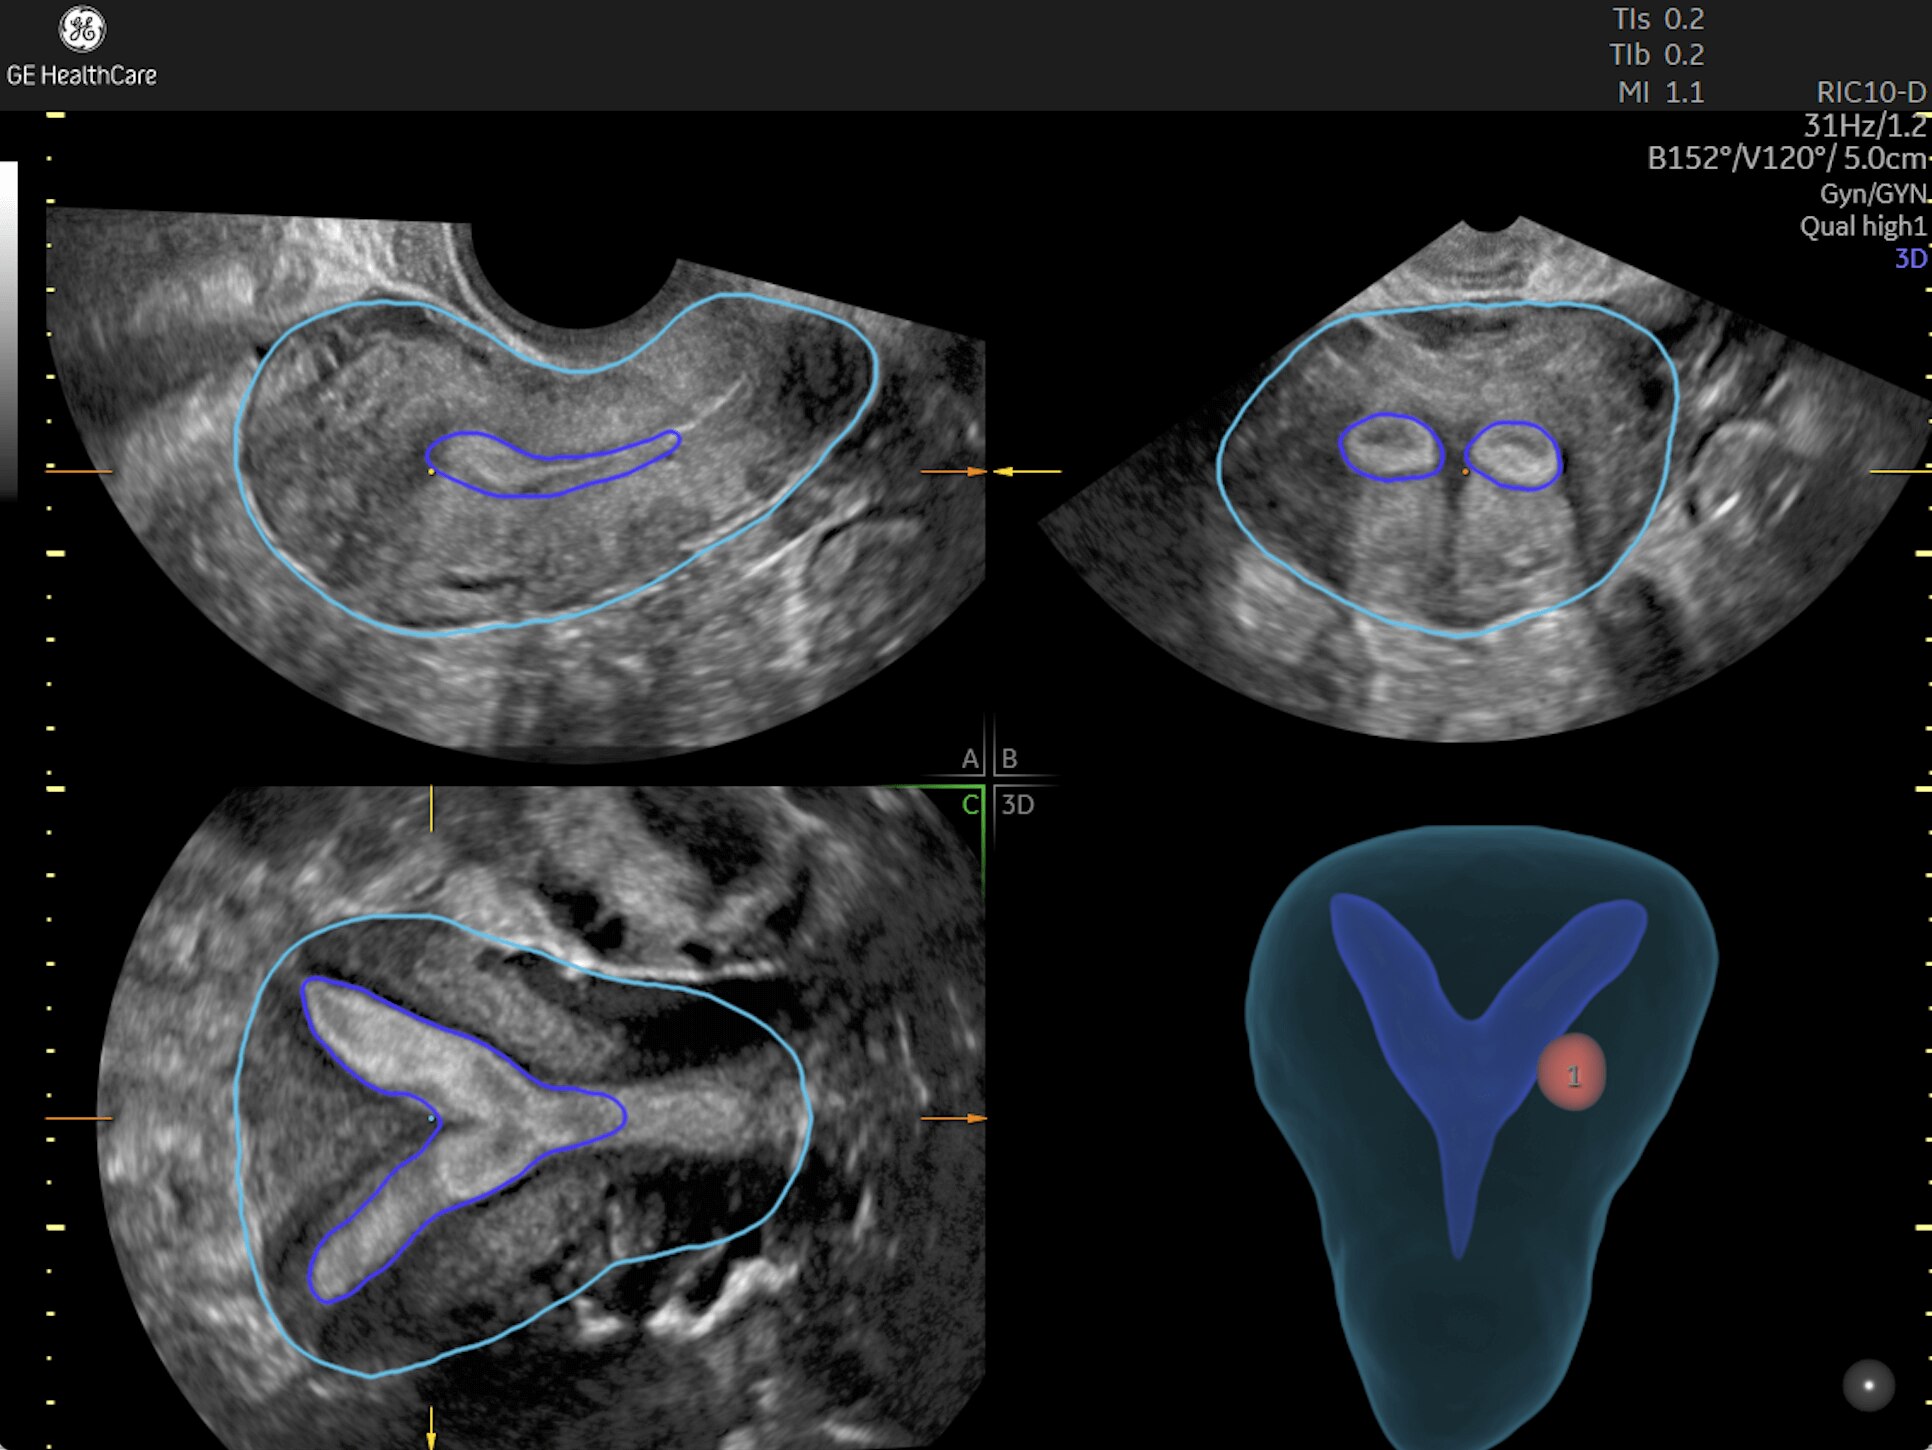

Pelvic Health

Offer patient answers faster with Ai-based automation tools

Complex cases come with enough uncertainty. That's why the Voluson Expert 22 is specifically designed for in-depth assessment of complicated anatomy — with pioneering first trimester, fetal cardiac, gynecological, and other pivotal technologies that focus on early detection and intervention.